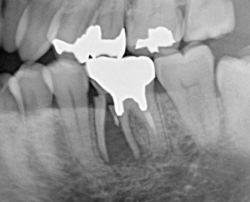

| 歯根破折の症例です。時々歯肉が腫れて痛む、咬むと痛いという症状があります。虫歯も無いのにおかしいなと思ったら、歯が割れていたなんて事があります。レントゲン写真で分かる場合もありますが、抜歯して初めて分かる場合もあります。元々健康な歯でも割れる事もありますので、硬い食べ物には気を付けましょう。 | ![]() ![]() ![]() ![]() |